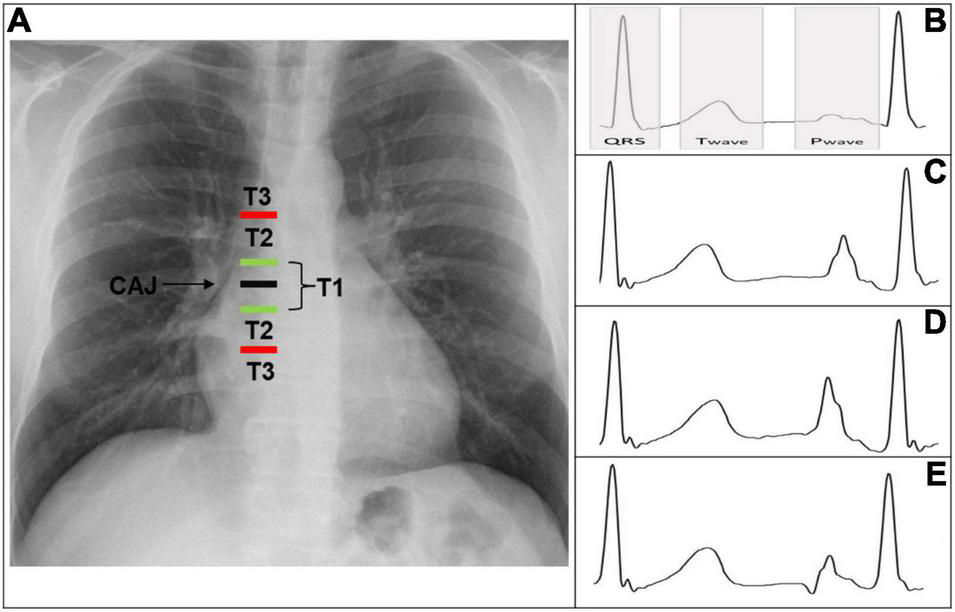

According to the distance from the tip to the CAJ, the PICC positions can be classified into three types (Figure 1A) (4).

T1: Tip is within 1 cm of the CAJ (optimal).

T2: Tip is between 1 and 3 cm from the CAJ (suboptimal).

T3: Tip is >3 cm below the CAJ or is not in the SVC (inadequate, needing repositioning).

(A) Chest X-ray displaying CAJ localization. Catheter tip in T1 (tip within 1 cm of the CAJ) is optimal. Catheter tip in T2 (tip within 1–3 cm of the CAJ) is suboptimal. Catheter tip in T3 (tip more than 3 cm below the CAJ or not in the SVC) is inadequate, needing repositioning. (B) Intracavitary electrocardiogram with overlay of the QRS complex zone, T-wave zone, and P-wave zone. A catheter tip in T3 that is not in the SVC will feature this trace, equivalent to the superficial ECG trace. (C) Intracavitary electrocardiogram with increasing P-wave (equivalent to the T wave). This is representative of a catheter tip approaching the CAJ in T2. (D) Intracavitary electrocardiogram with maximal P-wave without initial negative deflection. The tip is optimally positioned at the CAJ in the T1 zone (within 1 cm of the CAJ). (E) Intracavitary electrocardiogram with decreasing P-wave and initial negative deflection. This is representative of a catheter tip beyond the CAJ, in the T2–T3 zone. CAJ, cavo-atrial junction; SVC, superior vena cava.

As long as the catheter is distant from the central position, the P-wave remains unchanged and is equivalent to the superficial ECG trace.

The tip is not in the SVC, corresponding to a T3 position (Figure 1B).

As the tip nears the CAJ, the intracavitary P-wave slowly increases in amplitude.

The tip is within 3 cm of the CAJ, corresponding to a T2 position (Figure 1C).

At the moment the catheter is at the CAJ level, the P-wave will show its maximal amplitude without initial negative deflection (Figure 1D).

The tip is within 1 cm of the CAJ, corresponding to a T1 position (Figure 1D).

When the tip proceeds further than the CAJ, the P-wave will shrink again and present an initial negative deflection (Figure 1E) (25). The tip is far beyond the CAJ, corresponding to a T2–T3 position (Figure 1E).